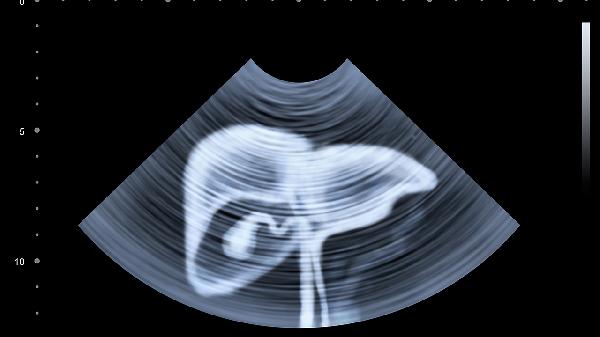

日常需保持规律作息,避免暴饮暴食及高脂饮食。疼痛发作时可尝试膝胸卧位缓解腹胀,记录疼痛特点及伴随症状供医生参考。若出现持续剧烈疼痛、发热、便血等警示症状须立即就医。定期体检有助于早期发现肝胆胰疾病,腹部超声是常用的初步筛查手段。